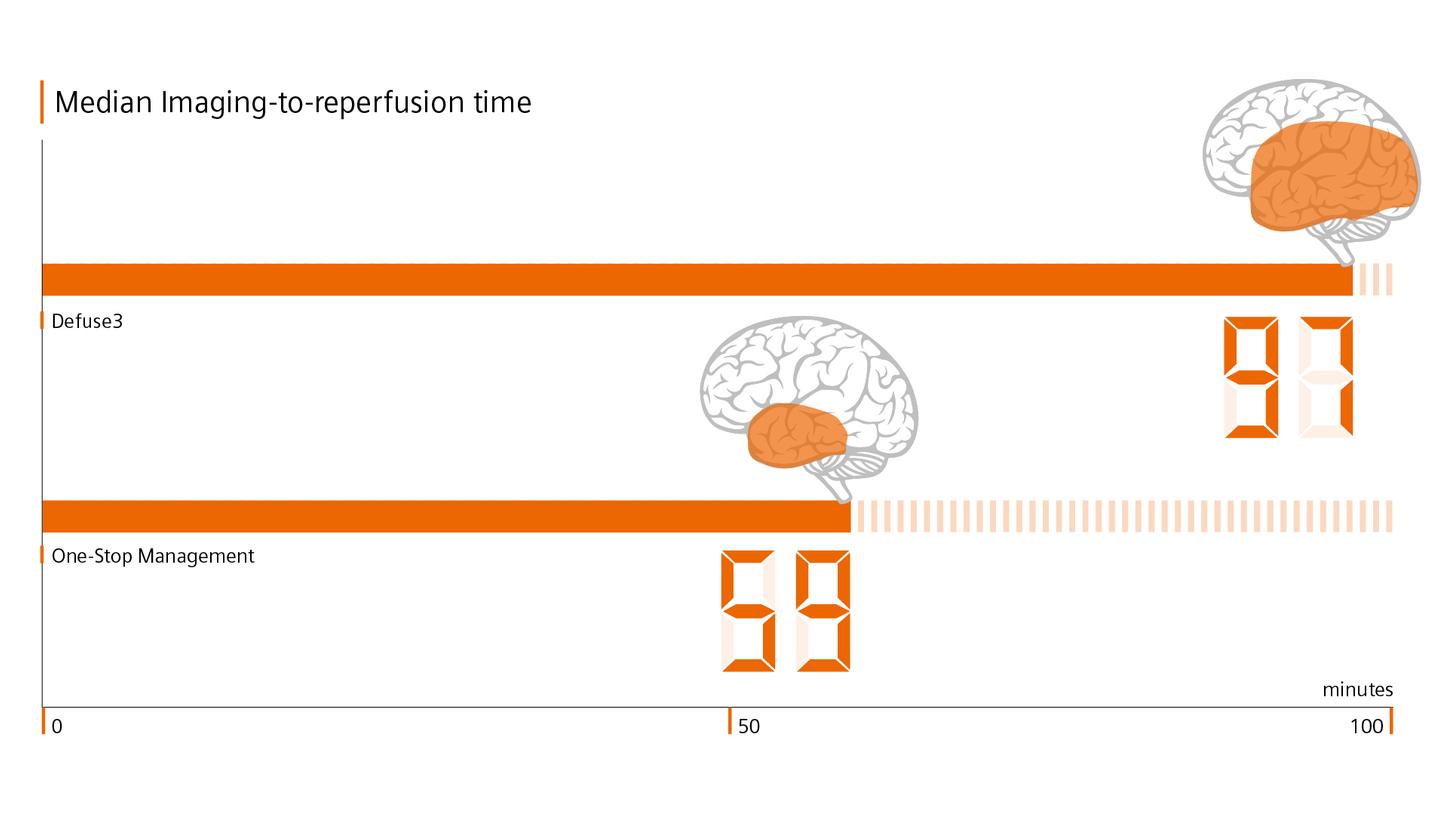

In recent years, various clinical trials have shown the advantages of performing endovascular thrombectomy in patients with a high stroke score as well as of one-stop stroke care.

In their study, M. Psychogios et al. have shown that diagnosing and treating potential LVO patients on one system can save valuable time and significantly improve functional outcome.6

In their study, M. Psychogios et al. have shown that diagnosing and treating potential LVO patients on one system can save valuable time and significantly improve functional outcome.6